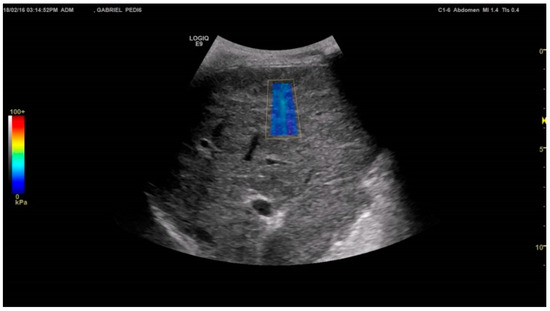

3.3. Two-Dimensional Shear Wave Elastography (2D-SWE)